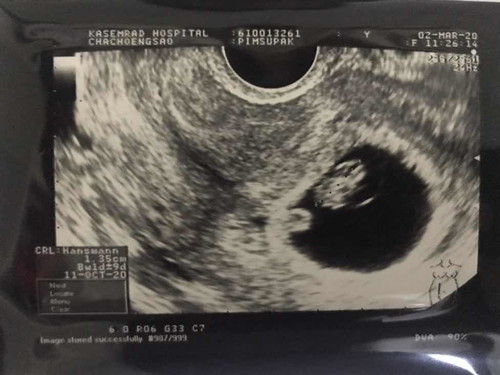

คือในใบอัลตราซาวด์อายุครรภ์วันที่ไปฝากครรภ์ครั้งแรกมันวันที่2/03 8+1(แต่คุณหมอลง8+6) วันถ้านับแล้วมาวันนี้ก็ต้อง12+1ใช่ไหมคะ แต่พอวันนี้หมอนับไปตรวจคุณหมอลงอายุครรภ์12+6 เราก็งงว่าจริงๆแล้วอายุครรภ์เท่าไหร่กันแน่ ใครรู้ช่วยบอกทีคะ ปล. ประจำเดือนครั้งสุดท้ายวันที่ 31 ธ.คหมด5ม.ค

ใบ ซาวน์เขียนว่า GA 8+- 9 ค่ะแปลว่าคลาดเคลื่อนได้ ที่คุณหมอลงไปว่า 8+6 คิดว่านับจากวันแรกของประจำเดือนครั้งสุดท้าย เพราะงั้นตอนนี้ถัดมา 1 เดือน ก็ 12+- 6 ค่า

อายุครรภ์ในเครื่องซาวน์ ประมาณจากขนาดทารกค่ะ แต่อายุครรภ์ที่หมอระบุ มาจากการคำนวณระยะเวลาไข่ตก ต้องยึดหมอเป็นหลักค่ะ ไม่ใช่เครื่องอัลตราซาวน์